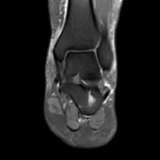

A patient presents with pain in the sole of the foot on both sides, especially on the left side, which occurs with exertion, particularly during the first steps in the morning.

The question of whether there are rheumatic manifestations or whether the complaints are mechanically induced should be clarified.

Mild plantar fasciitis and intraosseous ganglion of the calcaneus